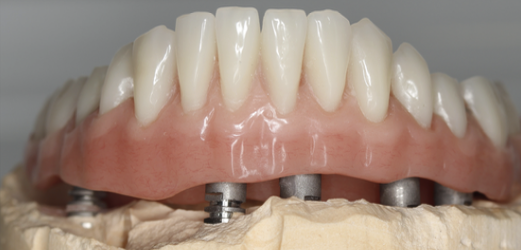

Mai întâi se realizează bara (Fig. 3.9.10) peste care se va aplica viitoarea lucrare. Apoi se realizează o machetă a lucrării pentru a analiza corectitudinea ocluziei (mușcăturii) (Fig. 3.9.11) precum și înălțimea dinților și aspectul facial al pacientului (Fig. 3.9.12, și Fig. 3.9.13).

Aspectul lucrării este unul natural, aceasta îmbunătățind estetica generală și fizionomia pacientului prin redarea conturului feței și plenitudinii obrajilor și a buzelor. Refacerea funcției masticatorii și redarea fizionomiei va aduce o îmbunătățire semnificativă a calității vieții pacienților care aleg acest tip de tratament (Fig. 3.9.15).